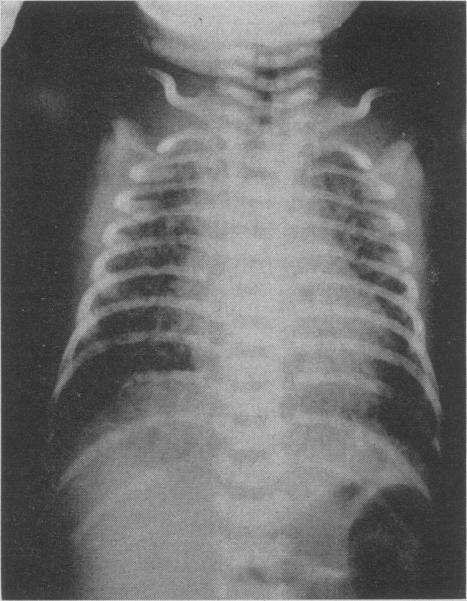

Four hundred and thirty infants selectively referred to the Newborn Unit of The Hospital for Sick Children, Toronto, with the symptom of respiratory distress, were reviewed. There were 142 cases of the "idiopathic respiratory distress syndrome" (IRDS), of which 67 were fatal. The remainder included 100 cardiac (76 deaths), 63 extra-pulmonary (28 deaths) and 109 other specific pulmonary conditions (54 deaths). Of the 109, half were due to massive aspiration. Serial observations and radiographs led to correct clinical diagnosis in 85% of necropsy-proved cases of IRDS and in a comparable proportion of all other conditions. The incidence and mortality rate of IRDS were twice as high in males as in females. A significant number of premature infants have transient respiratory distress after birth, and diagnostic criteria for inclusion in any study should be defined in detail. This study emphasized the large contribution of disorders of the respiratory and cardiac systems to neonatal mortality and led to the formation of a special department for intensive care and research in these conditions.

对430名因呼吸窘迫症状而被选择性转诊至多伦多病童医院新生儿科的婴儿进行了回顾性研究。其中有142例“特发性呼吸窘迫综合征”(IRDS),其中67例死亡。其余包括100例心脏疾病(76例死亡)、63例肺外疾病(28例死亡)和109例其他特定肺部疾病(54例死亡)。在这109例中,一半是由于大量吸入所致。系列观察和X光片检查使得85%经尸检证实的IRDS病例以及所有其他疾病中相当比例的病例得到了正确的临床诊断。IRDS的发病率和死亡率男性是女性的两倍。相当数量的早产儿出生后有短暂呼吸窘迫,任何研究中的纳入诊断标准都应详细界定。本研究强调了呼吸和心脏系统疾病对新生儿死亡率的巨大影响,并促使成立了一个针对这些病症的重症监护和研究特别科室。